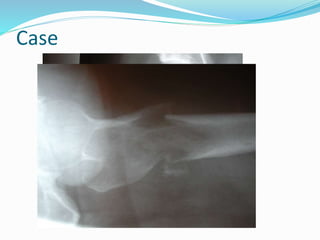

Brown Tumor

 pt looking well /bone scan

 Ca , ph , ALP

 PTH high

 Radiograph - osteopeina

 shoulder - sub periosteal ,sub chondral , Bone

 Hand resorpation

 spine sof tissue and chondral calcification

 skull